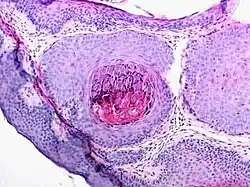

Obraz histologiczny

Zmiany histologiczne w zakażeniu MCV są bardzo charakterystyczne. Polegają na zrazikowatym przeroście naskórka połączonym z ogniskowym wnikaniem naskórka w głąb tkanki łącznej. W komórkach warstwy kolczystej naskórka obserwuje się liczne, początkowo kwasochłonne, później zasadochłonne cytoplazmatyczne wtręty, tzw. ciałka mięczakowate (molluscum bodies). Są to owalne, homogenne ciała o średnicy 15–35 μm; początkowo widoczne są w komórkach warstwy kolczystej naskórka, mogą jednak znaleźć się w keratynocytach każdej warstwy naskórka. W warstwie podstawnej naskórka można stwierdzić zwiększenie objętości keratynocytów, ich jądra również są powiększone. W warstwie kolczystej natomiast komórki posiadają jądra spłaszczone i zepchnięte na obwód. Zakażone komórki przesuwają się ku powierzchni i z warstwy rogowej "wysypują się" do światła krypt, utworzonych przez rozrastający się naskórek. Zmianom może towarzyszyć miernie nasilony odczyn zapalny. Komórki z ciałkami mięczakowatymi stwierdza się także w preparacie z wyciśniętych z guzka mas, wybarwionym metodą Giemsy.